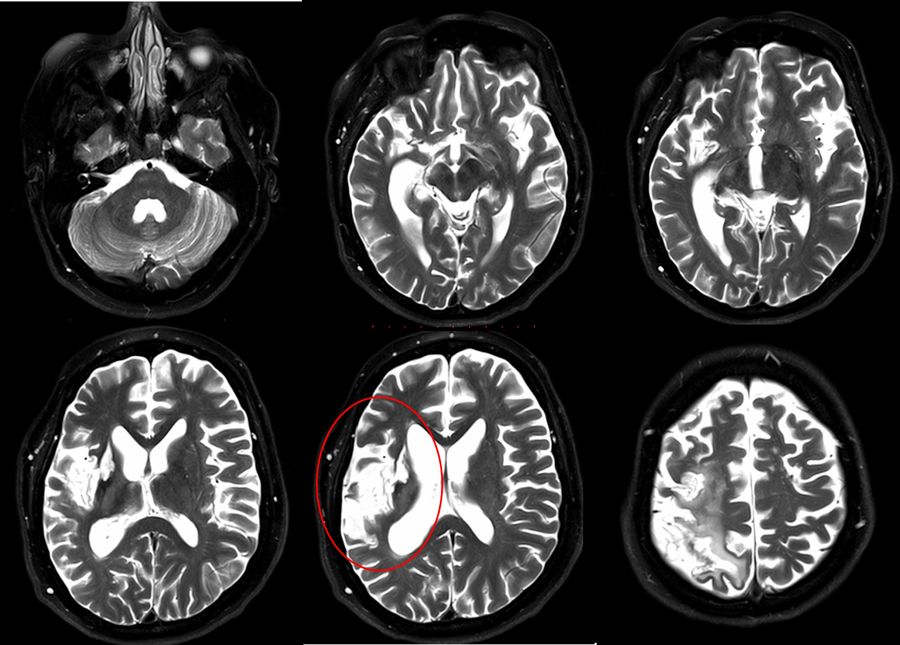

Post-surgery assessment

The postoperative CT scan showed no signs of postoperative complications. The presurgical area of ischemia in the territory the right MCA was also observed. The patient showed no additional postoperative neurological deficits and was discharged three days post-surgery.